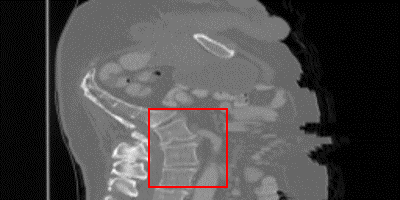

\stackanchorCase 2

\stackanchorHRPSNR/SSIM

\stackanchorDA-VSR34.91/0.980

\stackanchorDA-VSRNAsubscriptDA-VSR𝑁𝐴\textrm{DA-VSR}_{NA}34.78/0.976

\stackanchorSAINT34.84/0.977

\stackanchorSMORE34.65/0.978

\stackanchor3DRDN34.47/0.966

\stackanchor3DRCAN34.60/0.965

\stackanchorBicubic31.60/0.926

Figure 2: Visual comparisons of DA-VSR and other state-of-the-art implementations from the sagittal plane, highlight regions are contrast-adjusted. Case 1 is from the Colon dataset, Case 2 and 3 are from the Kidney dataset[7]. In particular, Case 3 is a lung region cropped from a kidney-containing image. Please refer to the supplemental material for more visual comparisons.

While metrics like PSNR and SSIM are useful to understand performance in aggregate, they can often be too coarse. Domain drift does not happen uniformly on a CT image. Some patches do not suffer as much since similar patches can be observed in the training set, leading to similar overall PSNR metrics; however, some patches suffer heavily due to lack of observations. We provide visualization on SR results, as shown in Fig. 2, to better show where improvements are most often observed. We observe that supervised techniques without adaptation can lead to significant overfitting issues over unseen test sets and create unfaithful details, as seen in Case 2 of Fig. 2 and indicated by the orange arrows. Compared to supervised methods, SMORE produces results that are smoother and more similar to the groundtruth if those patterns are seen in axial slices. For organs that exhibit different patterns between axial and other axes, such as the sagittal spinal structure, SMORE can generate unreliable or overly smooth patterns, as shown in Case 1 of Fig. 2. In comparison, since DA-VSR goes through supervised training on a lung dataset, which contains both LR and HR spine patterns, we observe that it performs much better than SMORE even with adaptation. Interestingly, we also observe improvements over the few unseen cases where a region of lung is included, e.g. in Case 3, by using our proposed adaptation stage. Despite being trained on the lung dataset, other supervised methods still experience local discontinuity over small scale bone structures. In this case, SMORE generates smoother but less structurally reliable details. DA-VSR takes the advantages of both approaches and generate smoother and more reliable details under this challenging case. As no two individuals are the same, DA-VSR’s ability to reduce minor distribution differences can be valuable in real SR applications.